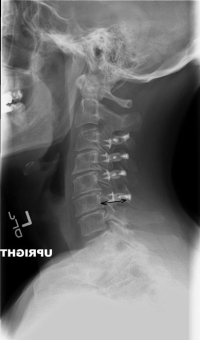

(Click to Enlarge Image) Preoperative lateral x-ray of the cervical spine. The black double arrow notes the reduced diameter of the spinal canal causing compression of the spinal cord.